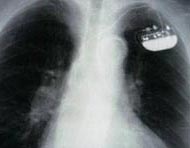

A pacemaker is a small device implanted in the chest. It sends electrical signals to start or regulate a slow heartbeat. It's most often placed in the chest just under the collarbone. A pacemaker may be used if the heart's natural pacemaker (the SA node) is not working correctly, causing a slow heart rate or rhythm, or if the electrical pathways are blocked.

An implantable cardioverter defibrillator (ICD) looks similar to a pacemaker, though slightly larger. It works very much like a pacemaker. But the ICD can send an energy shock that resets an abnormal heartbeat back to normal.

What are the parts of a pacemaker or an ICD?

A typical pacemaker or ICD has three main parts:

A pulse generator with a sealed lithium battery. It sends out the electrical signals that make the heart beat, or it sends out an electrical shock. Most generators can also receive and respond to signals sent by the heart itself.

One or more wires (leads). Leads are insulated flexible wires. They conduct electrical signals between the heart and the pulse generator. One end of the lead is attached to the pulse generator, and the electrode end of the lead is positioned in the heart. In the case of a biventricular pacemaker, leads are placed on both ventricles.

Electrodes. These are found on each lead.

Your doctor will make a small incision just under the collarbone. They will insert the pacemaker or ICD lead or leads into the heart through a blood vessel that runs under the collarbone. Once the lead is in place, your doctor can test it to make sure it is in the right place and is working. They then attach the lead to the generator (battery), which is placed just under the skin through the incision made earlier. Your doctor will close the incision with stitches, staples, or a medical glue (adhesive) and apply a dressing. Once the procedure has been completed, you will go through a recovery period of several hours.